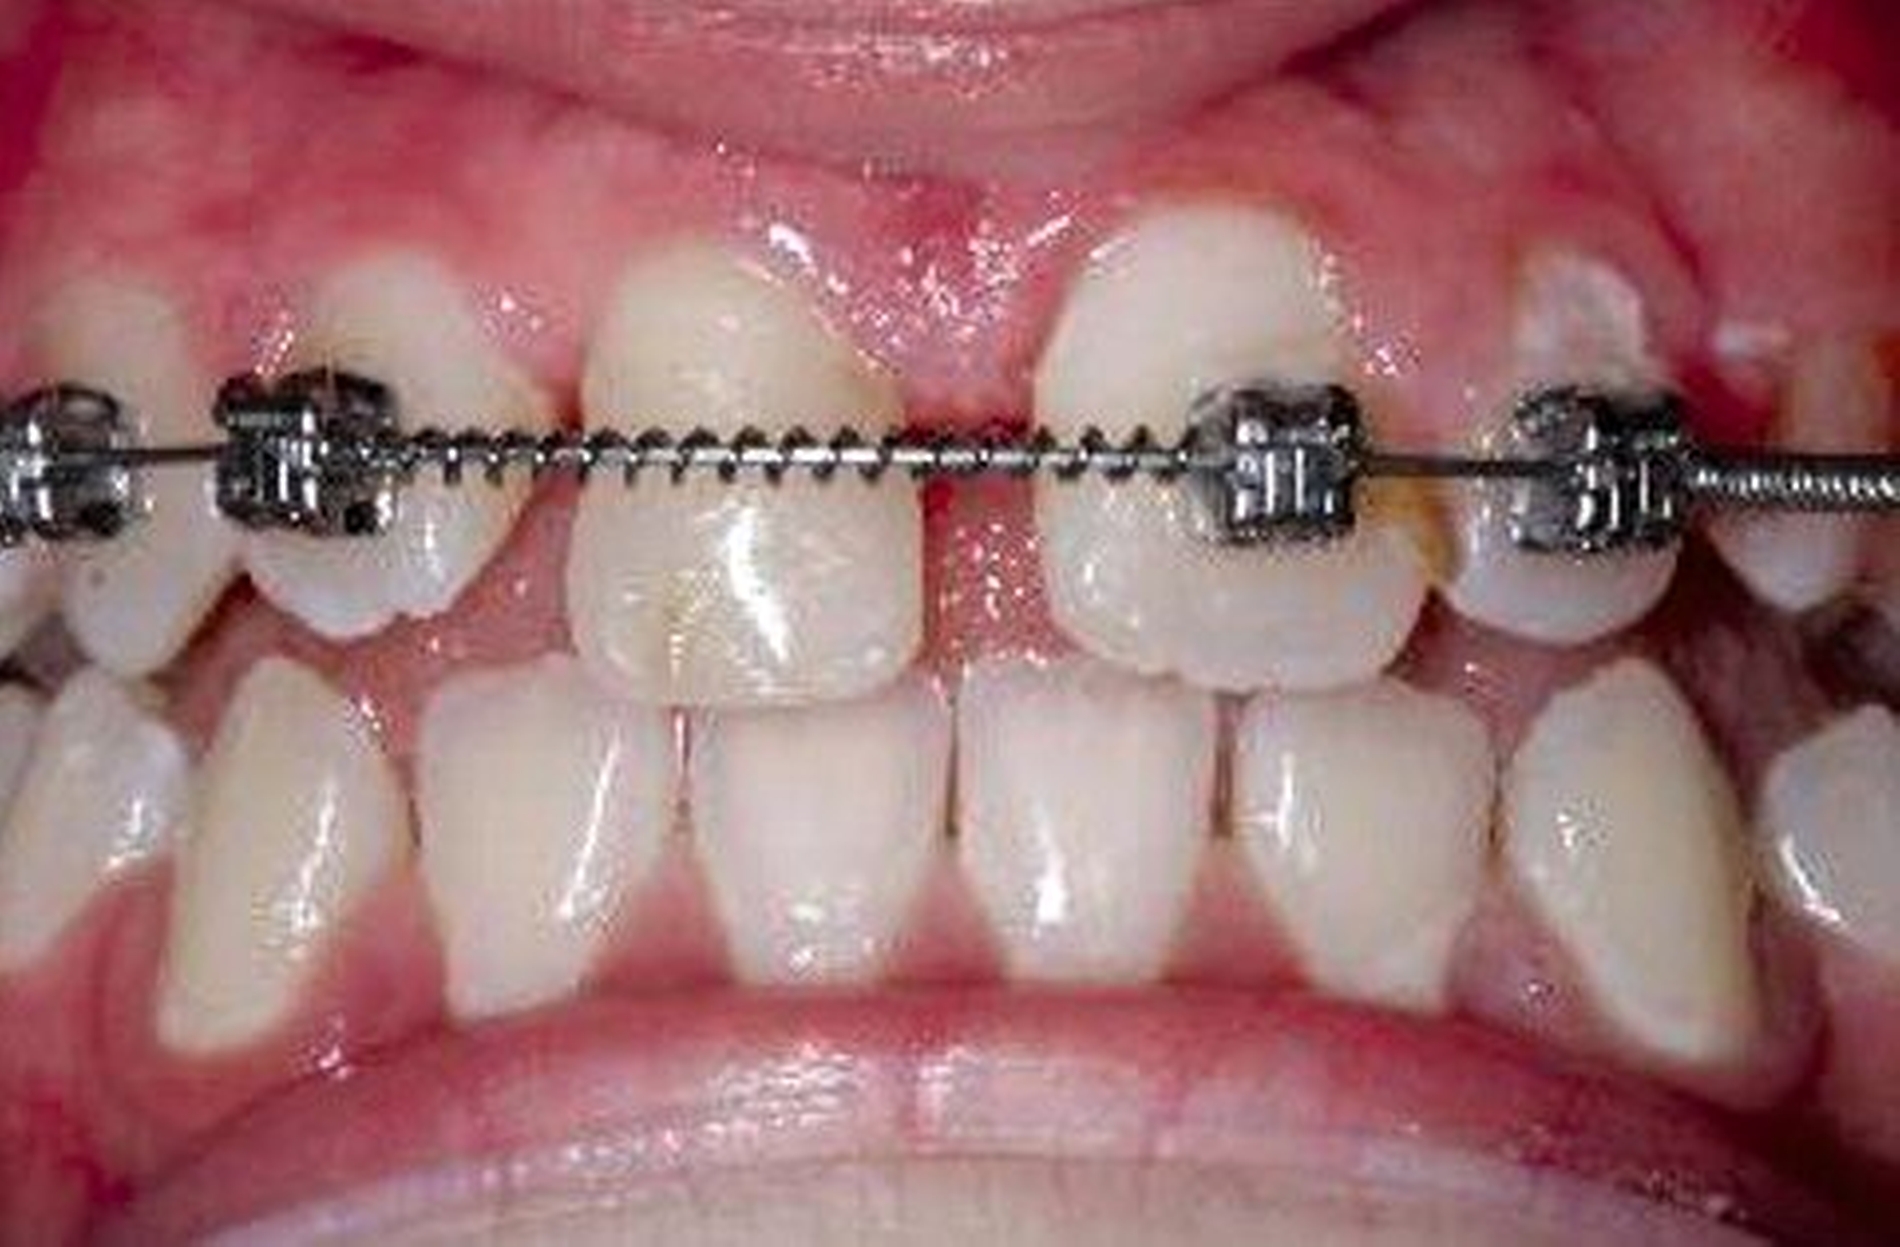

Zeitnah nach der chirurgischen Anluxation ist eine sich anschließende kieferorthopädische Extrusion in derartigen Fällen wünschenswert, weil dadurch der fehlende Alveolarknochen und die fehlende Gingiva augmentiert werden können. Nichtsdestotrotz ist in der Mehrzahl der Fälle mit einer erneuten Ankylosierung und dem Fortschreiten der Ersatzgewebsresorption in der neu eingestellten Position zu rechnen.

Der ankylosierte Zahn wird schonend gelöst („anluxiert“), bei Bedarf auch osteotomiert und aus seiner ursprünglichen Infraposition und/oder Verlagerung in die Okklusionsposition zum gesunden Nachbarzahn gestellt. Das Ziel dieser Maßnahme ist es, das vertikale Defizit durch die Ankylose-bedingte Wachstumshemmung aufzufangen (Abbildung 3). Je nach dem Zeitpunkt der Maßnahme und dem Verlauf kann der Zahn so vom frühen bis ins späte Wechselgebiss, in günstigen Fällen auch bis ins Erwachsenenalter, erhalten werden. Ob später ein kieferorthopädischer Lückenschluss, eine Prämolaren-Transplantation oder eine Implantation folgt, muss individuell nach der weiteren abzuschätzenden Prognose des Zahnes und nach dem Patientenwunsch entschieden werden.